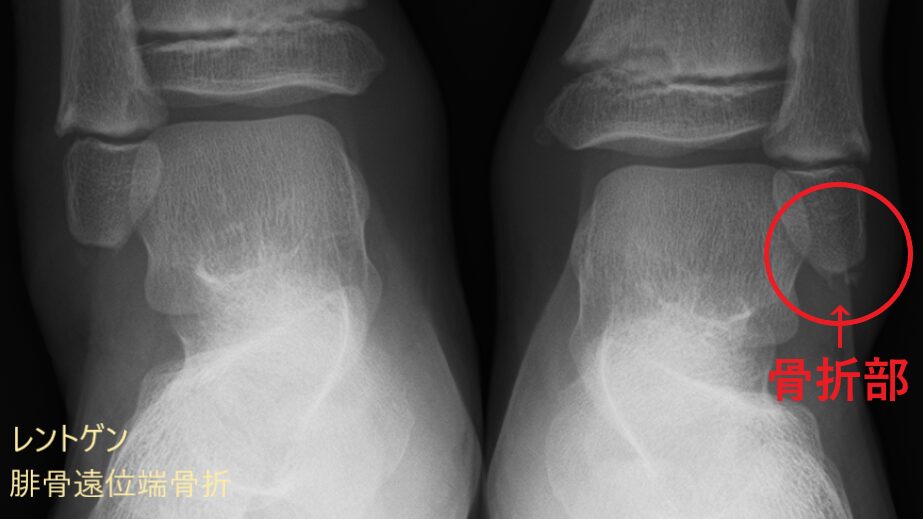

超音波(エコ-)検査は、骨・靭帯・筋肉・腱などの病態を診る検査装置です。

超音波検査の特長として、身体への負担が少ない点が挙げられます。レントゲンやCTのように放射線を使用しないため、お子さまや妊娠中の方にも配慮した検査が可能です。安全性が高く、状態の変化を確認する目的で繰り返し行えることも利点のひとつです。

レントゲン画像には映りにくい筋肉や腱、靭帯などの状態に加え、骨の様子もあわせて確認できます。